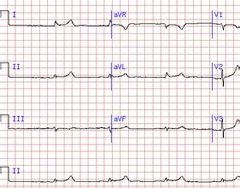

冠状动脉粥样硬化性心脏病

疾病介绍:冠状动脉粥样硬化性心脏病是冠状动脉血管发生动脉粥样硬化病变而引起血管腔狭窄或阻塞,造成心肌缺血、缺氧或坏死而导致的心脏病,常常被称为“冠心病…【详细】